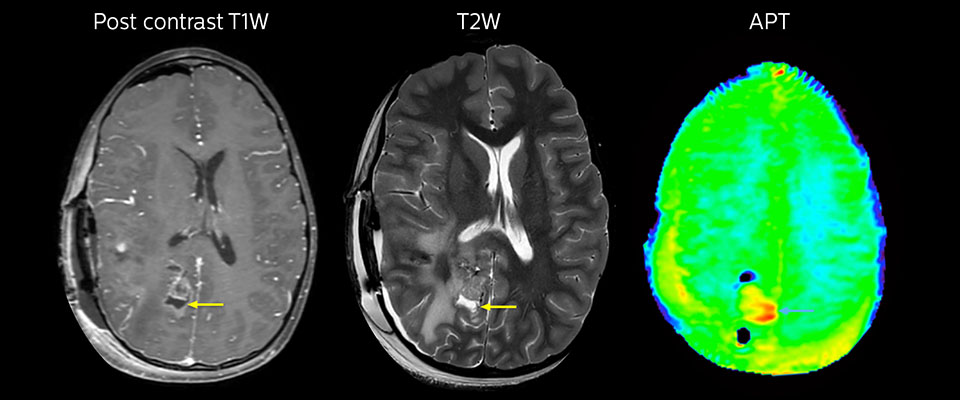

APT-Bildgebung eines niedrig differenzierten Tumors

Niedrig differenziertes Gliom bei einem 5-jährigen Patienten mit Neurofibromatose 1. Diese niedrig differenzierte Läsion zeigt auf kontrastverstärkten Bildern keine Anreicherung, aber ein mittelgradiges APT-Signal. Die Stabilität der Läsion über die Zeit bestätigt, dass es sich um eine pathologische Veränderung niedriger Differenzierung handelt.